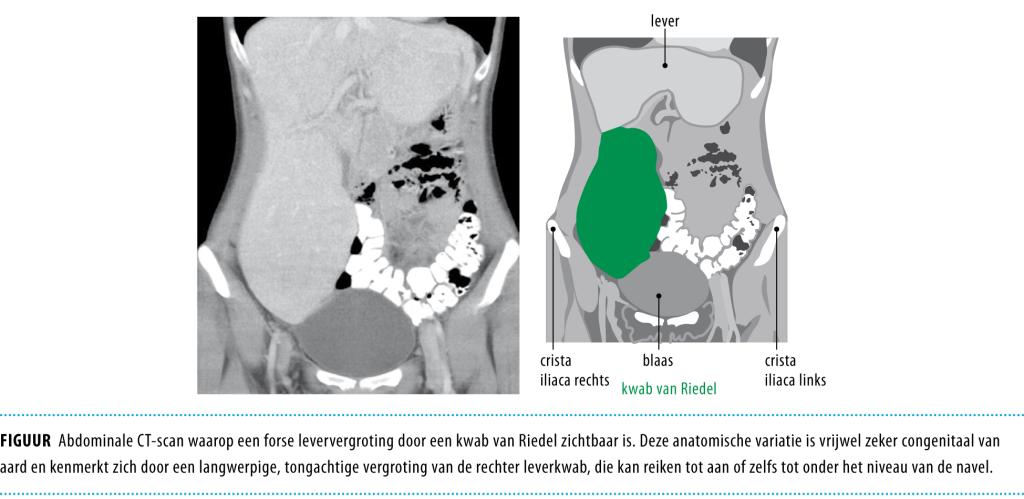

Wij verrichtten opnieuw beeldvormend onderzoek (CT en MRI). De 2 leverafwijkingen vertoonden kenmerken, zoals een centraal litteken, die pasten bij focale nodulaire hyperplasie, maar zij vormden geen verklaring voor de hepatomegalie. De leververgroting bleek te berusten op een homogene, gladde, sterk vergrote rechter leverkwab, die reikte tot in het kleine bekken (figuur). Op grond hiervan luidde de diagnose ‘hepatomegalie door een kwab van Riedel’.

Een kwab van Riedel is een anatomische variatie met een langwerpige, tongachtige vergroting van de rechter leverkwab, tot aan of zelfs tot onder het niveau van de navel. Het betreft vrijwel zeker een congenitale afwijking. Herkenning van de diffuse, selectief vergrote rechter leverkwab is voldoende voor de diagnose. Deze kan gesteld worden door echografie, CT of MRI. Een kwab van Riedel hoort thuis in de differentiaaldiagnose van een palpabele massa aan de rechterzijde van de buik of bij hepatomegalie.

Figuur 1